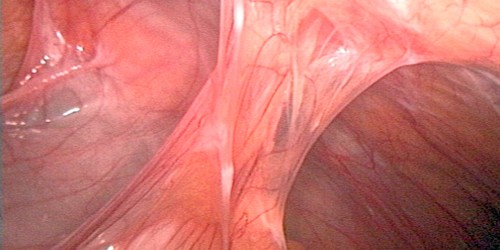

Maria del Mar Hernandez158915 over a year ago I would like to know about nanofiber biodegradable use to remove gallbladder adhesions. Thanks. Loading...